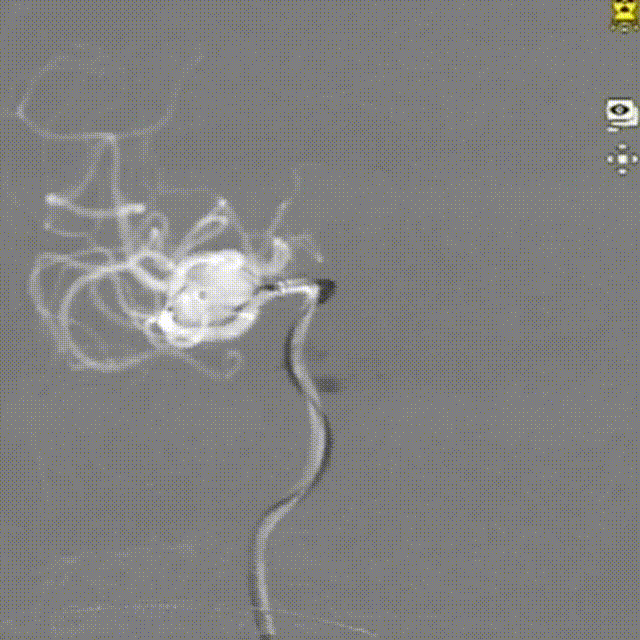

造影显示:右侧大脑中动脉分叉部动脉瘤,和大脑中动脉走行一致,动脉瘤偏长,不规则,有凸起的子囊,主要累及上干。

动脉瘤测量

右侧大脑中动脉分叉部动脉瘤:动脉瘤约为13.3*8.1mm(H*W),瘤颈宽约为4.8mm。

造影提示动脉瘤瘤颈部血流进入缓慢,造影剂滞留明显,但是载瘤动脉覆盖略多。

再次造影,瘤囊内血流进一步减弱、造影剂明显滞留。

解脱后,工作角度和侧位减影像、非减影像造影,以及透视图和三维重建提示WEB™顺应动脉瘤囊形态良好,瘤内血流明显变缓,分叉部上下干分支血流通畅。